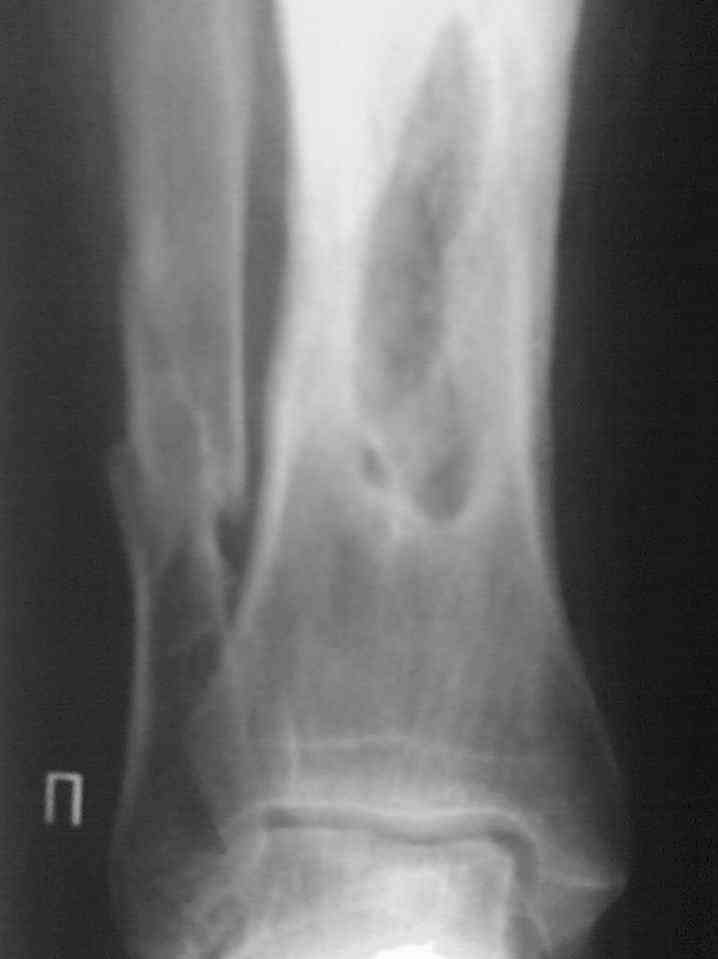

Здравствуйте коллеги! Прошу помочь с лечением больного. Мужчина в полном расцвете сил в апреле 2004 года получил травму - открытый оскольчатый перелом голени. Через 2 дня произведён МОС большеберцовой кости пластиной АО и винтами. Послеоперационный период осложнился остеомиелитом. Через 3.5 месяца пластина удалена. В марте 2005 года оперативное лечение в г. Екатеринбурге - санирование очага, некрэктомия. В июне 2006 года в ОКБ произведена секвестрэктомия, через неделю некрэктомия. Неоднократно получал антибактериальную терапию, в результате чего сформировалась сенсибилизация ко многим антибактериальным препаратам. В данный получает перевязки. Локально сохраняется кратерообразная гнойная рана, размерами до 4 х 3 см. Хотелось бы узнать Ваши мнения по поводу дальнейшего ведения данного пациента.

Выкладываю снимки в хронологическом порядке. Снмки все какие есть у больного.

Количество не заменяет качества, поэтому не стоит выкладывать весь хлам, какой удастся найти у пациента. Лучше сделать 1)свежие 2)хорошего качества рентгенограммы, чтобы оценивать ситуацию по ним, а не по мутным огрызкам.

Пока в любом случае надо выполнять туалет и перевязки несколько раз в сутки, лаваж любой водой, можно водным хлоргексидином. Делать повторные обработки, некрэктомии. Наверно, ферменты будут полезны. Надо в любом случае тут добиваться сначала санации раны. Смотреть на дефект и думать, что делать, будем потом.

Даже если недоступны более современные варианты типа vacuum assisted closure или спейсеров из костного цемента с антибиотиками, вид раны не вызывает паники, доступные хирургические методы должны обеспечить санацию.